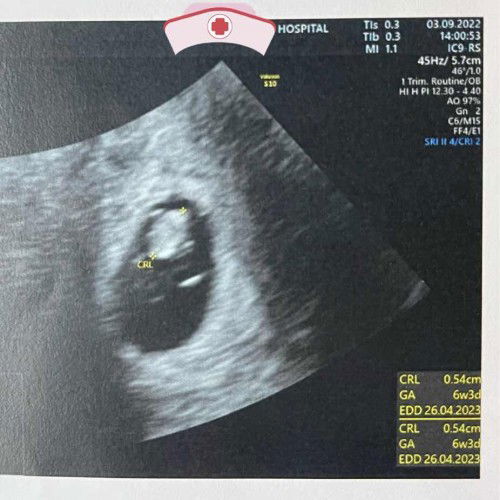

20/8/22 พบคุณหมอ อัลตร้าซาวน์ ไม่เจอตัวน้อง ภาพอัลตร้าซาวน์ อายุครรภ์ 6w0d 3/9/22 คุณหมอนัดตรวจซ้ำ เจอตัวน้อง เจอเสียงหัวใจเต้น แต่ภาพอัลตร้าซาวน์ อายุครรภ์ 6w3d ซึ่งจริงๆ ผ่านมา 2w มันควรจะเห็นเป็น 8w0d มีบ้านไหนเคยเป็น แบบนี้บ้างคะ ขอคำแนะนำหน่อย เนื่องจากคุณหมอแจ้งว่า อายุครรภ์ มันไม่สอดคล้องกับวันที่ ปจด มาครั้งสุดท้าย แต่ถ้าไม่มองเรื่องอื่น มองแค่อายุครรภ์ตามอัลตร้าซาวน์ ล่าสุด ถือว่าน้องเติบโตได้ปกติ แต่ถ้าดูเทียบกับอย่างอื่น คุณหมอบอกยังหาเหตุผลอธิบายไม่ได้เลย ว่าน้อง จะสามารถเคิบโตได้จริงไหม เลยยังไม่รับฝากครรภ์ รอนัดตรวจซ้ำอีกที 1 เดือนข้างหน้า